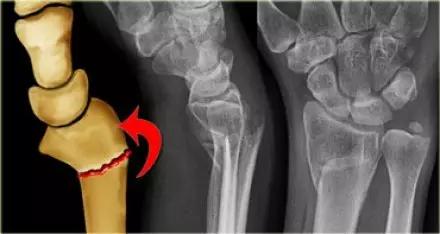

2. Colles 骨折

桡骨远端骨折,伴有桡骨远端向背侧的移位,可以有或没有尺骨干的骨折。具有这几个特征:背侧粉碎、向背侧成角、向背侧移位且挠骨短缩的关节外骨折。

典型 colles 骨折,枪刺样、餐叉样畸形

3. Smith 骨折

桡骨远端骨折伴骨折远端向掌侧移位,也称为反 Colles 骨折。

来源:radiology assistant